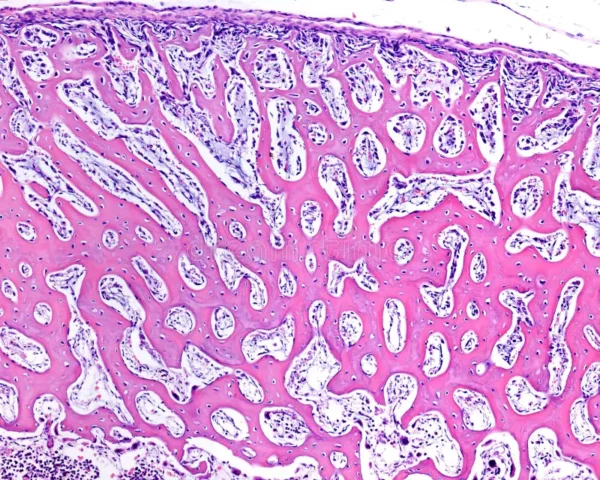

La esqueletogénesis constituye un proceso biológico altamente orquestado que refleja, en su complejidad, la historia evolutiva prolongada de los vertebrados. La razón por la cual distintos linajes celulares participan en…